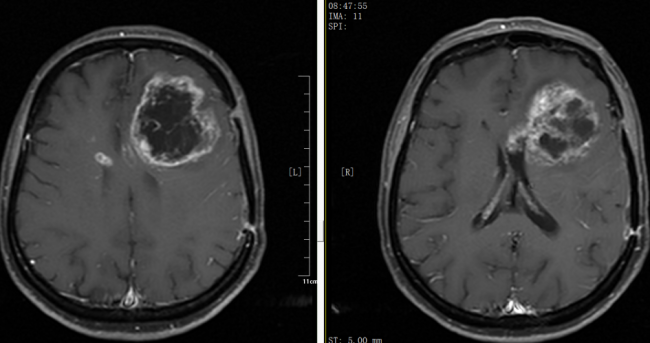

银丰(济南)医院神经肿瘤科成功为胶质母细胞瘤患者实施左额叶病损切除术

胶质母细胞瘤是恶性程度极高的原发性脑肿瘤,病情进展快、治疗难度大,严重威胁患者生命。近日,银丰(济南)医院神经肿瘤科团队成功救治了一例术后复发进展的高级别胶质母细胞瘤患者。

从子宫到肺,再到大脑——抗癌十三载患者在银丰(济南)医院神经肿瘤科成功接受开颅肿瘤切除术,再现希望之光

"当抗癌长征跨越十三载,肿瘤从子宫转移至肺部,又进一步侵袭大脑,生命的防线该如何坚守?近日,银丰(济南)医院神经肿瘤科团队迎难而上,成功为一位病程长达十三年的子宫内膜癌脑转移患者实施开颅肿瘤切除术